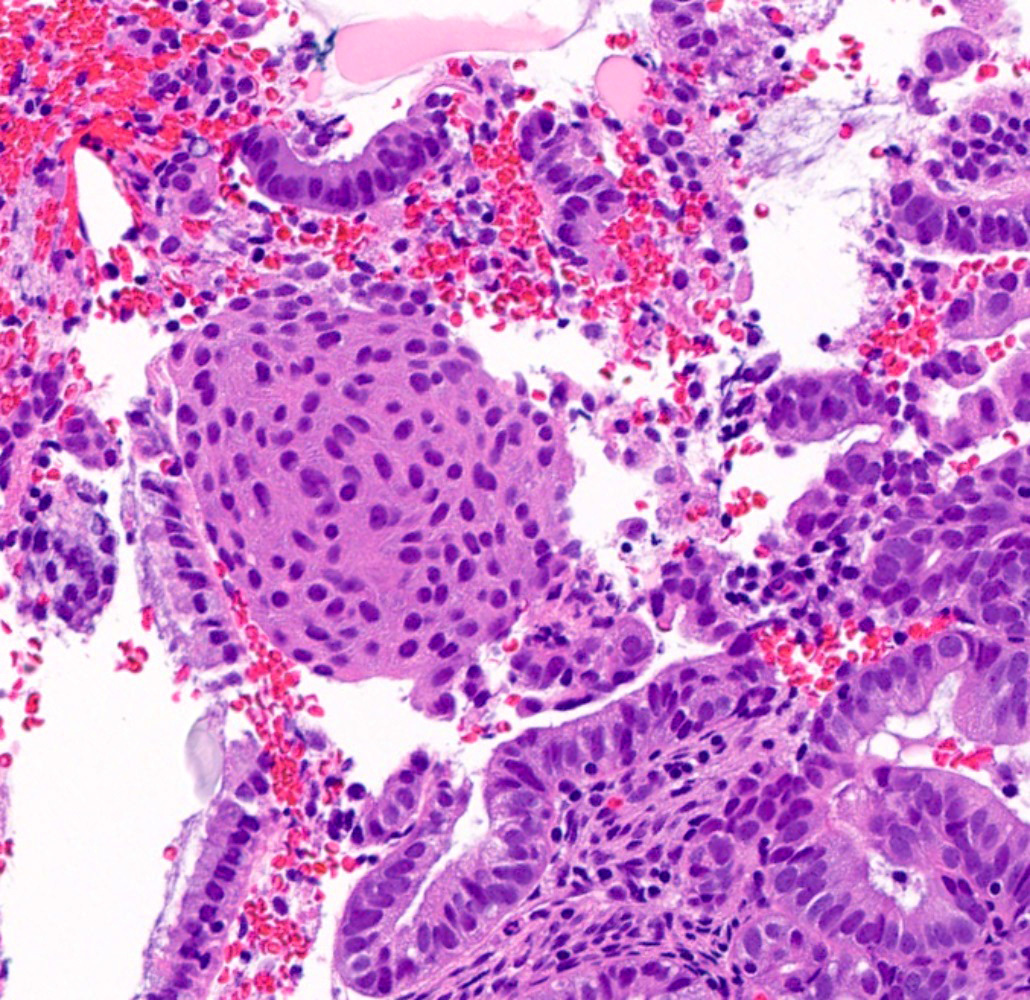

Microscopic (histologic) images

Contributed by Jessica L. Bentz, M.D.

- Morular (Gynecol Endocrinol 2020;36:460):

- Rounded to polygonal nests of immature squamous cells that fill the glandular lumen

- Rarely demonstrates keratinization, mitoses and central necrosis

- Generally cytologically bland but can obscure examination of the glandular architecture

- Morular borders are not well defined

- Characteristic intercellular bridges are not identified

- More commonly associated with endometrioid adenocarcinoma